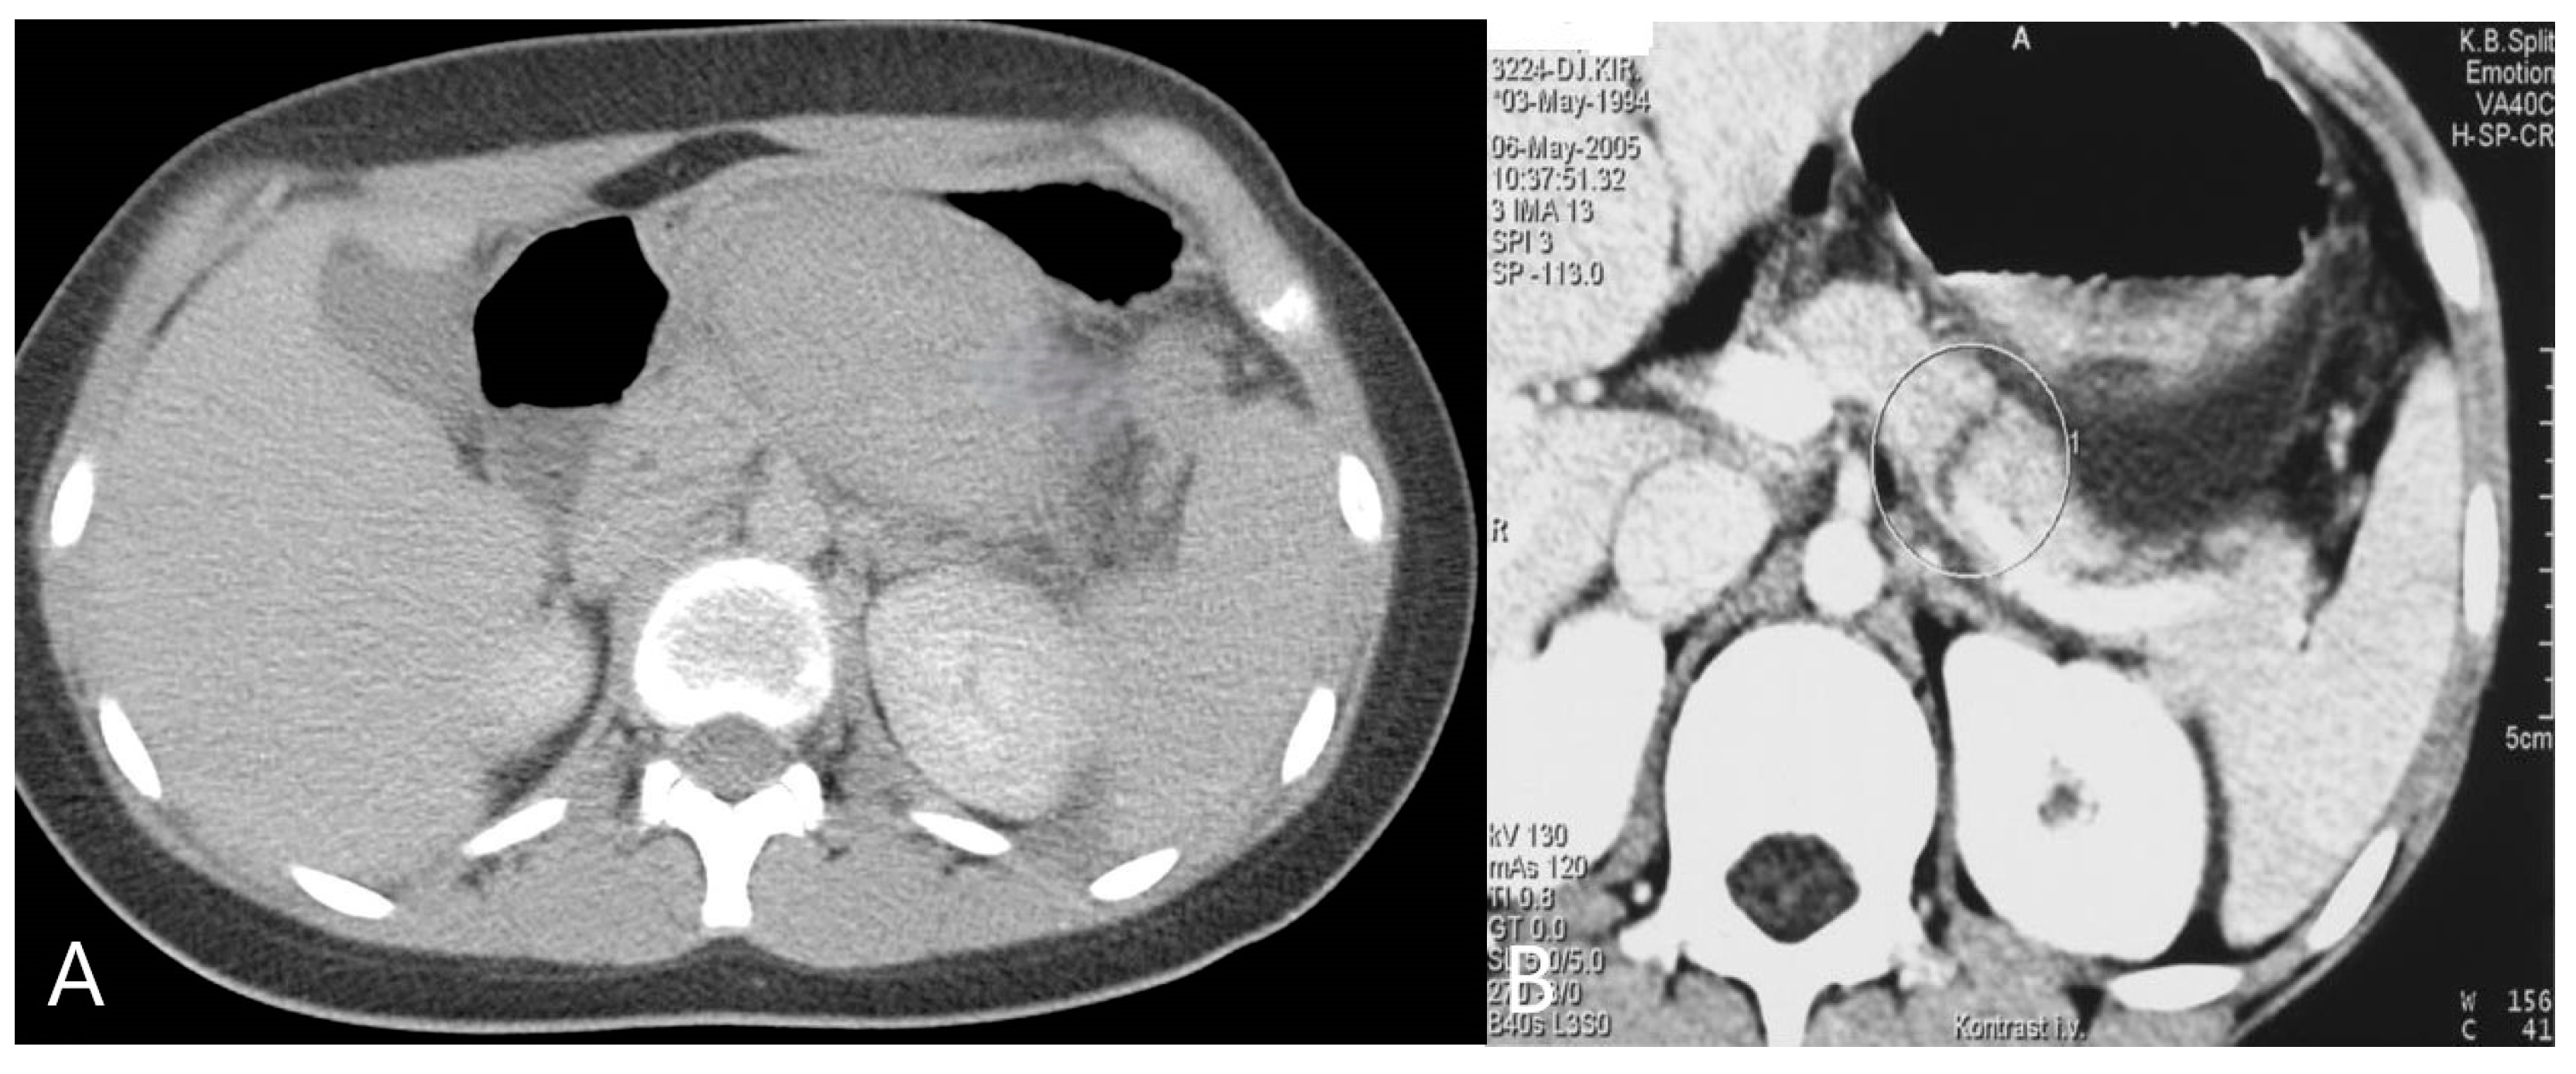

- Zakaria, O.M.; Daoud, M.Y.I.; Zakaria, H.M.; Al Naim, A.; Al Bshr, F.A.; Al Arfaj, H.; Al Abdulqader, A.A.; Al Mulhim, K.N.; Buhalim, M.A.; Al Moslem, A.R.; et al. Management of pediatric blunt abdominal trauma with split liver or spleen injuries: A retrospective study. Pediatr. Surg. Int. 2023, 39, 106. [Google Scholar] [CrossRef]